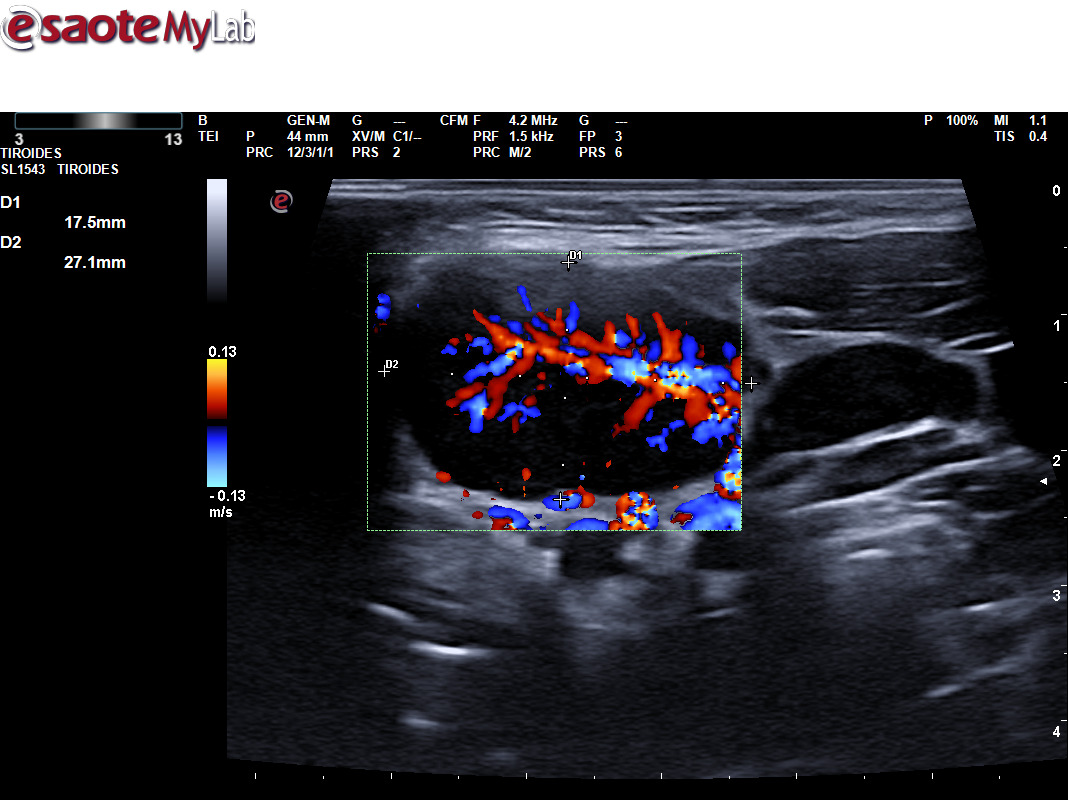

A través de distintos casos clínicos queremos valorar la importancia de la ecografía clínica en pacientes que consultan por la aparición de una masa cervical. Tras valorar a varios pacientes que han consultado por una masa cervical, hemos realizado una sesión clínica formativa sobre el aprendizaje de la ecografía cervical. Durante este periodo hemos podido diagnosticar diferentes patologías utilizando ecografía clínica y apoyándonos en otras pruebas complementarias, como un tumor de Merkel, un tumor de Warthin, una mononucleosis infecciosa, inflamación de un ganglio linfático por infección, un adenoma pleomorfo en glándula submandibular, malformación vascular, microlitiasis parotídeas, tuberculosis y un mieloma múltiple.

La ecografía ayuda a determinar las características de la masa, como su tamaño, forma y consistencia, lo que puede ayudarnos en la sospecha de patología maligna.

Permite distinguir entre diferentes tipos de tejidos, como quistes, ganglios linfáticos inflamados o tumores, lo que es crucial para un diagnóstico adecuado.

También, ayuda a ver si la masa está afectando a estructuras cercanas, lo que puede ser relevante para el tratamiento.